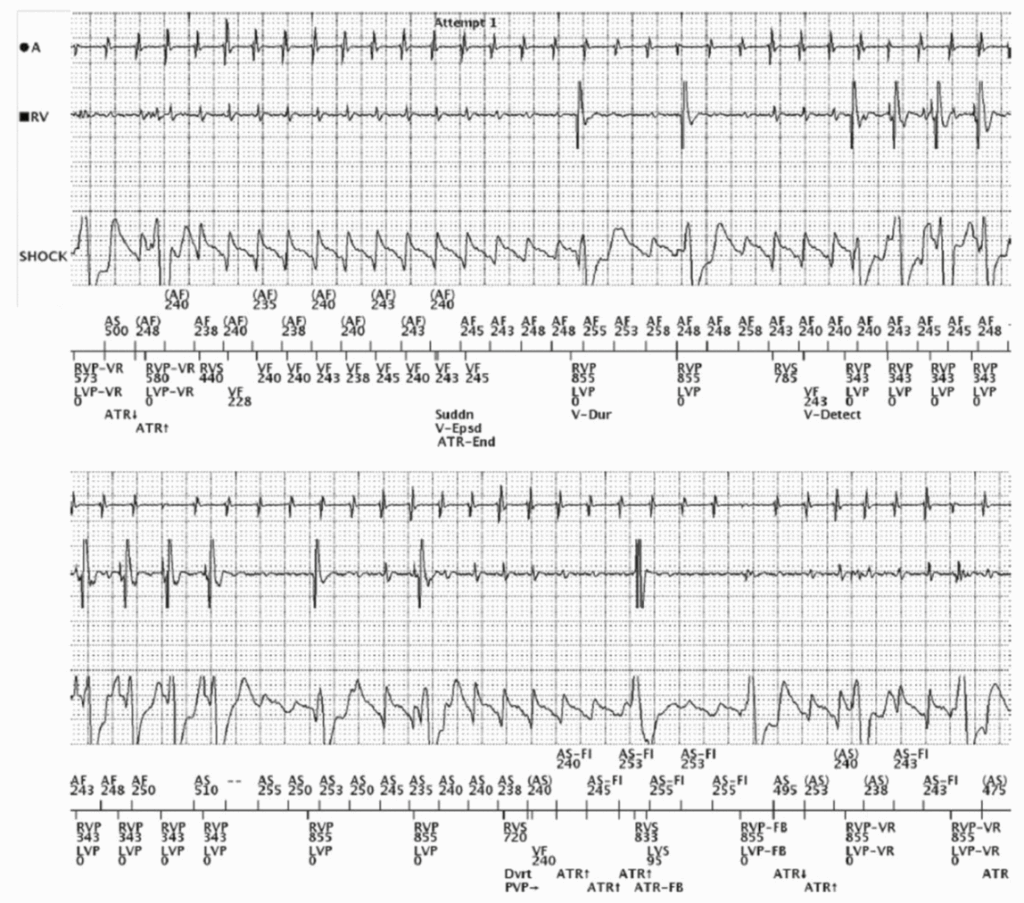

Dual tachycardia

AF & VT